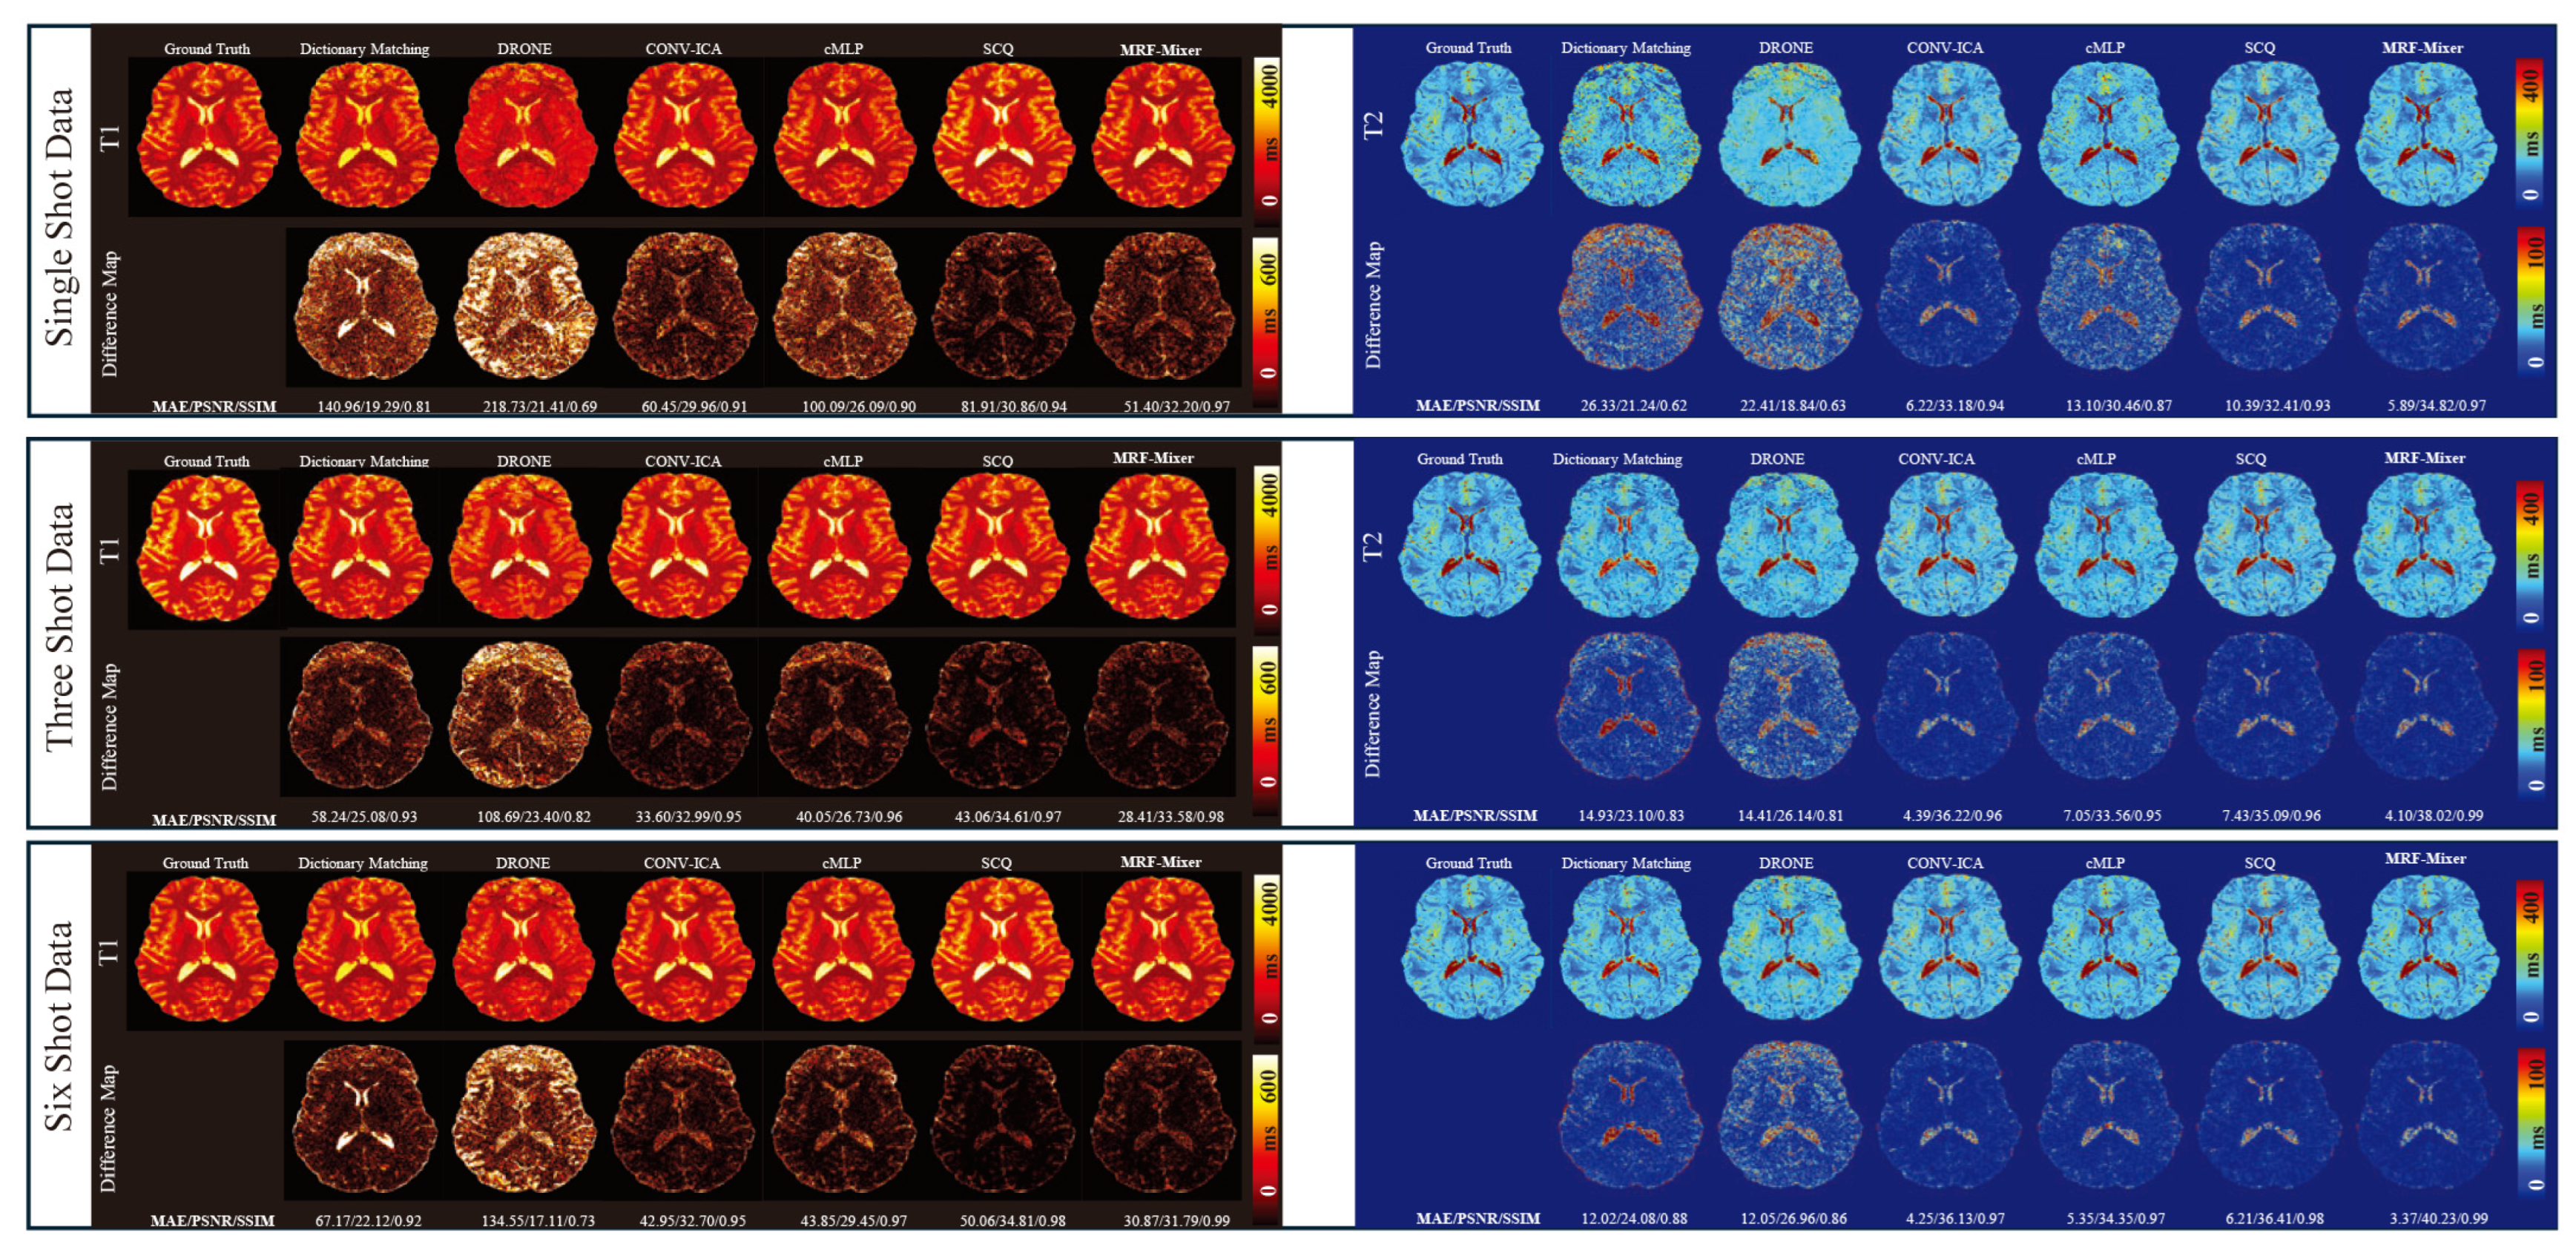

3.2. Simulation Results

3.3. In Vivo Experimental Results